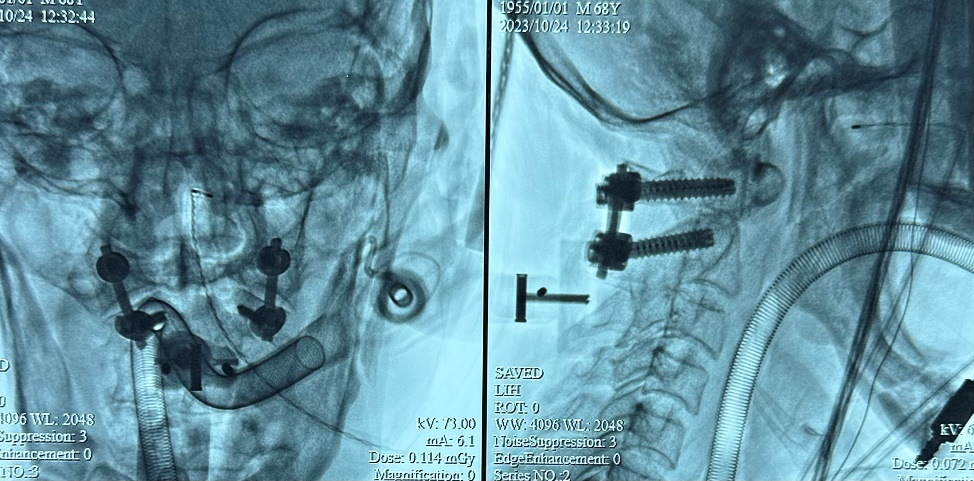

检查显示颈椎X线正侧位示内固定位置良好

西安市红会医院脊柱病医院郝定均院长、脊柱病医院创伤与老年脊柱病区许正伟主任团队综合考虑患者病情特点后,为其制定手术方案,进行MAZOR X骨科手术机器人辅助下行寰枢椎切开复位椎弓根螺钉内固定术,患者术后恢复良好。